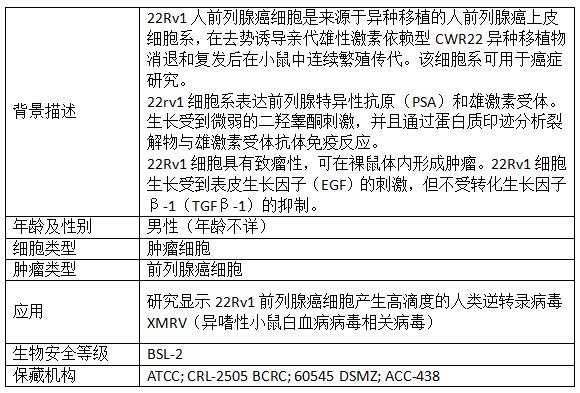

产品信息:

【1】Weeraratna AT, Dalrymple SL, Lamb JC, Denmeade SR, Miknyoczki S, Dionne CA, Isaacs JT. Pan-trk inhibition decreases metastasis and enhances host survival in experimental models as a result of its selective induction of apoptosis of prostate cancer cells. Clin Cancer Res. 2001 Aug;7(8):2237-45. PMID: 11489797.

【2】Kuzmin I, Gillespie JW, Protopopov A, Geil L, Dreijerink K, Yang Y, Vocke CD, Duh FM, Zabarovsky E, Minna JD, Rhim JS, Emmert-Buck MR, Linehan WM, Lerman MI. The RASSF1A tumor suppressor gene is inactivated in prostate tumors and suppresses growth of prostate carcinoma cells. Cancer Res. 2002 Jun 15;62(12):3498-502. PMID: 12067994.

【3】Mendoza N, Phillips GL, Silva J, Schwall R, Wickramasinghe D. Inhibition of ligand-mediated HER2 activation in androgen-independent prostate cancer. Cancer Res. 2002 Oct 1;62(19):5485-8. PMID: 12359757.